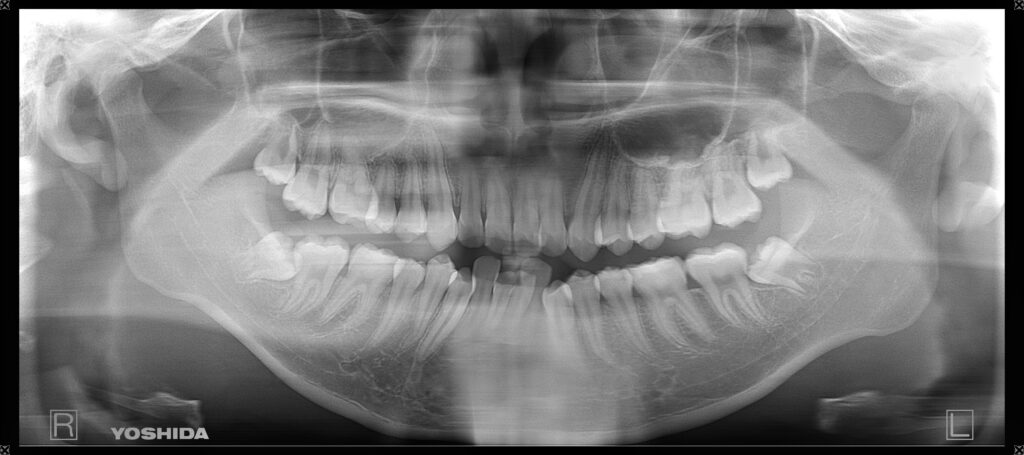

①親知らず抜歯前